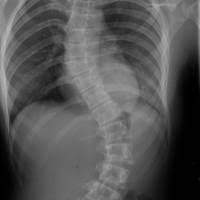

La lumbalgia es una de las afecciones más comunes entre la población adulta, como resultado de una postura inadecuada o cargar objetos pesados sin la técnica correcta, este padecimiento es incapacitante, informó el Instituto Mexicano del Seguro Social (IMSS) en Veracruz Sur. El especialista en Medicina Física y Rehabilitación del Hospital General de Zona (HGZ) No. 35 de Cosamaloapan, doctor Rafael Hernández Martínez, explicó que la población adulta puede sufrir hasta dos episodios de lumbalgia en su vida, que se traduce en un dolor intenso que impide realizar sus actividades diarias. "No debemos olvidar que la columna es una articulación de carga movible, la columna cervical tiene sus arcos de movilidad, al igual que la dorsal y la lumbar que la vuelve blanco de lesiones al tener movimientos repetitivos y hacer cargas excesivas sin la protección necesaria", explicó. En consulta, mencionó el especialista, son los trabajadores de ingenios y de la construcción los más afectados al cargar objetos muy pesados y no utilizan la técnica correcta para levantar y transportar cargas, afectando de manera importante su columna lumbar y cervical principalmente. Al cargar objetos de más de 10 kilos la columna empieza a sufrir, y si existe un grado de desviación, escoliosis o propensa a tener una arquitectura defectuosa, hay más posibilidad de presentar dolor. El doctor Hernández Martínez explicó la técnica para levantar objetos de suelo que consiste en separar los pies, flexionar las rodillas y elevar poco a poco la carga acercándolo al cuerpo, así como utilizar un cinturón o fajilla. Otra causa de daño a la columna es realizar deporte excesivo sin la instrucción profesional, especialmente en jóvenes que cargan pesas sin conocer técnicas y sin saber si es el peso adecuado para sus características físicas. "Por la competición que hay entre los jóvenes para ver quién carga más peso hacen levantamientos sin tener conocimiento, ocasionando un daño a su columna que quizá al inicio sea sólo un dolor; sin embargo, las consecuencias serán a futuro", explicó. Como recomendación para el cuidado de la columna es comer sanamente, realizar ejercicio como caminar, trotar o nadar, y no realizar cargas de peso repetitivas, o bien utilizar una fajar lumbar. El especialista en Medicina Física y de Rehabilitación hizo la invitación a la población usuaria a acudir de manera inmediata a la Unidad de Medicina Familiar del IMSS cuando haya una molestia en la columna a fin de detectar de manera oportuna y dar manejo especializado.